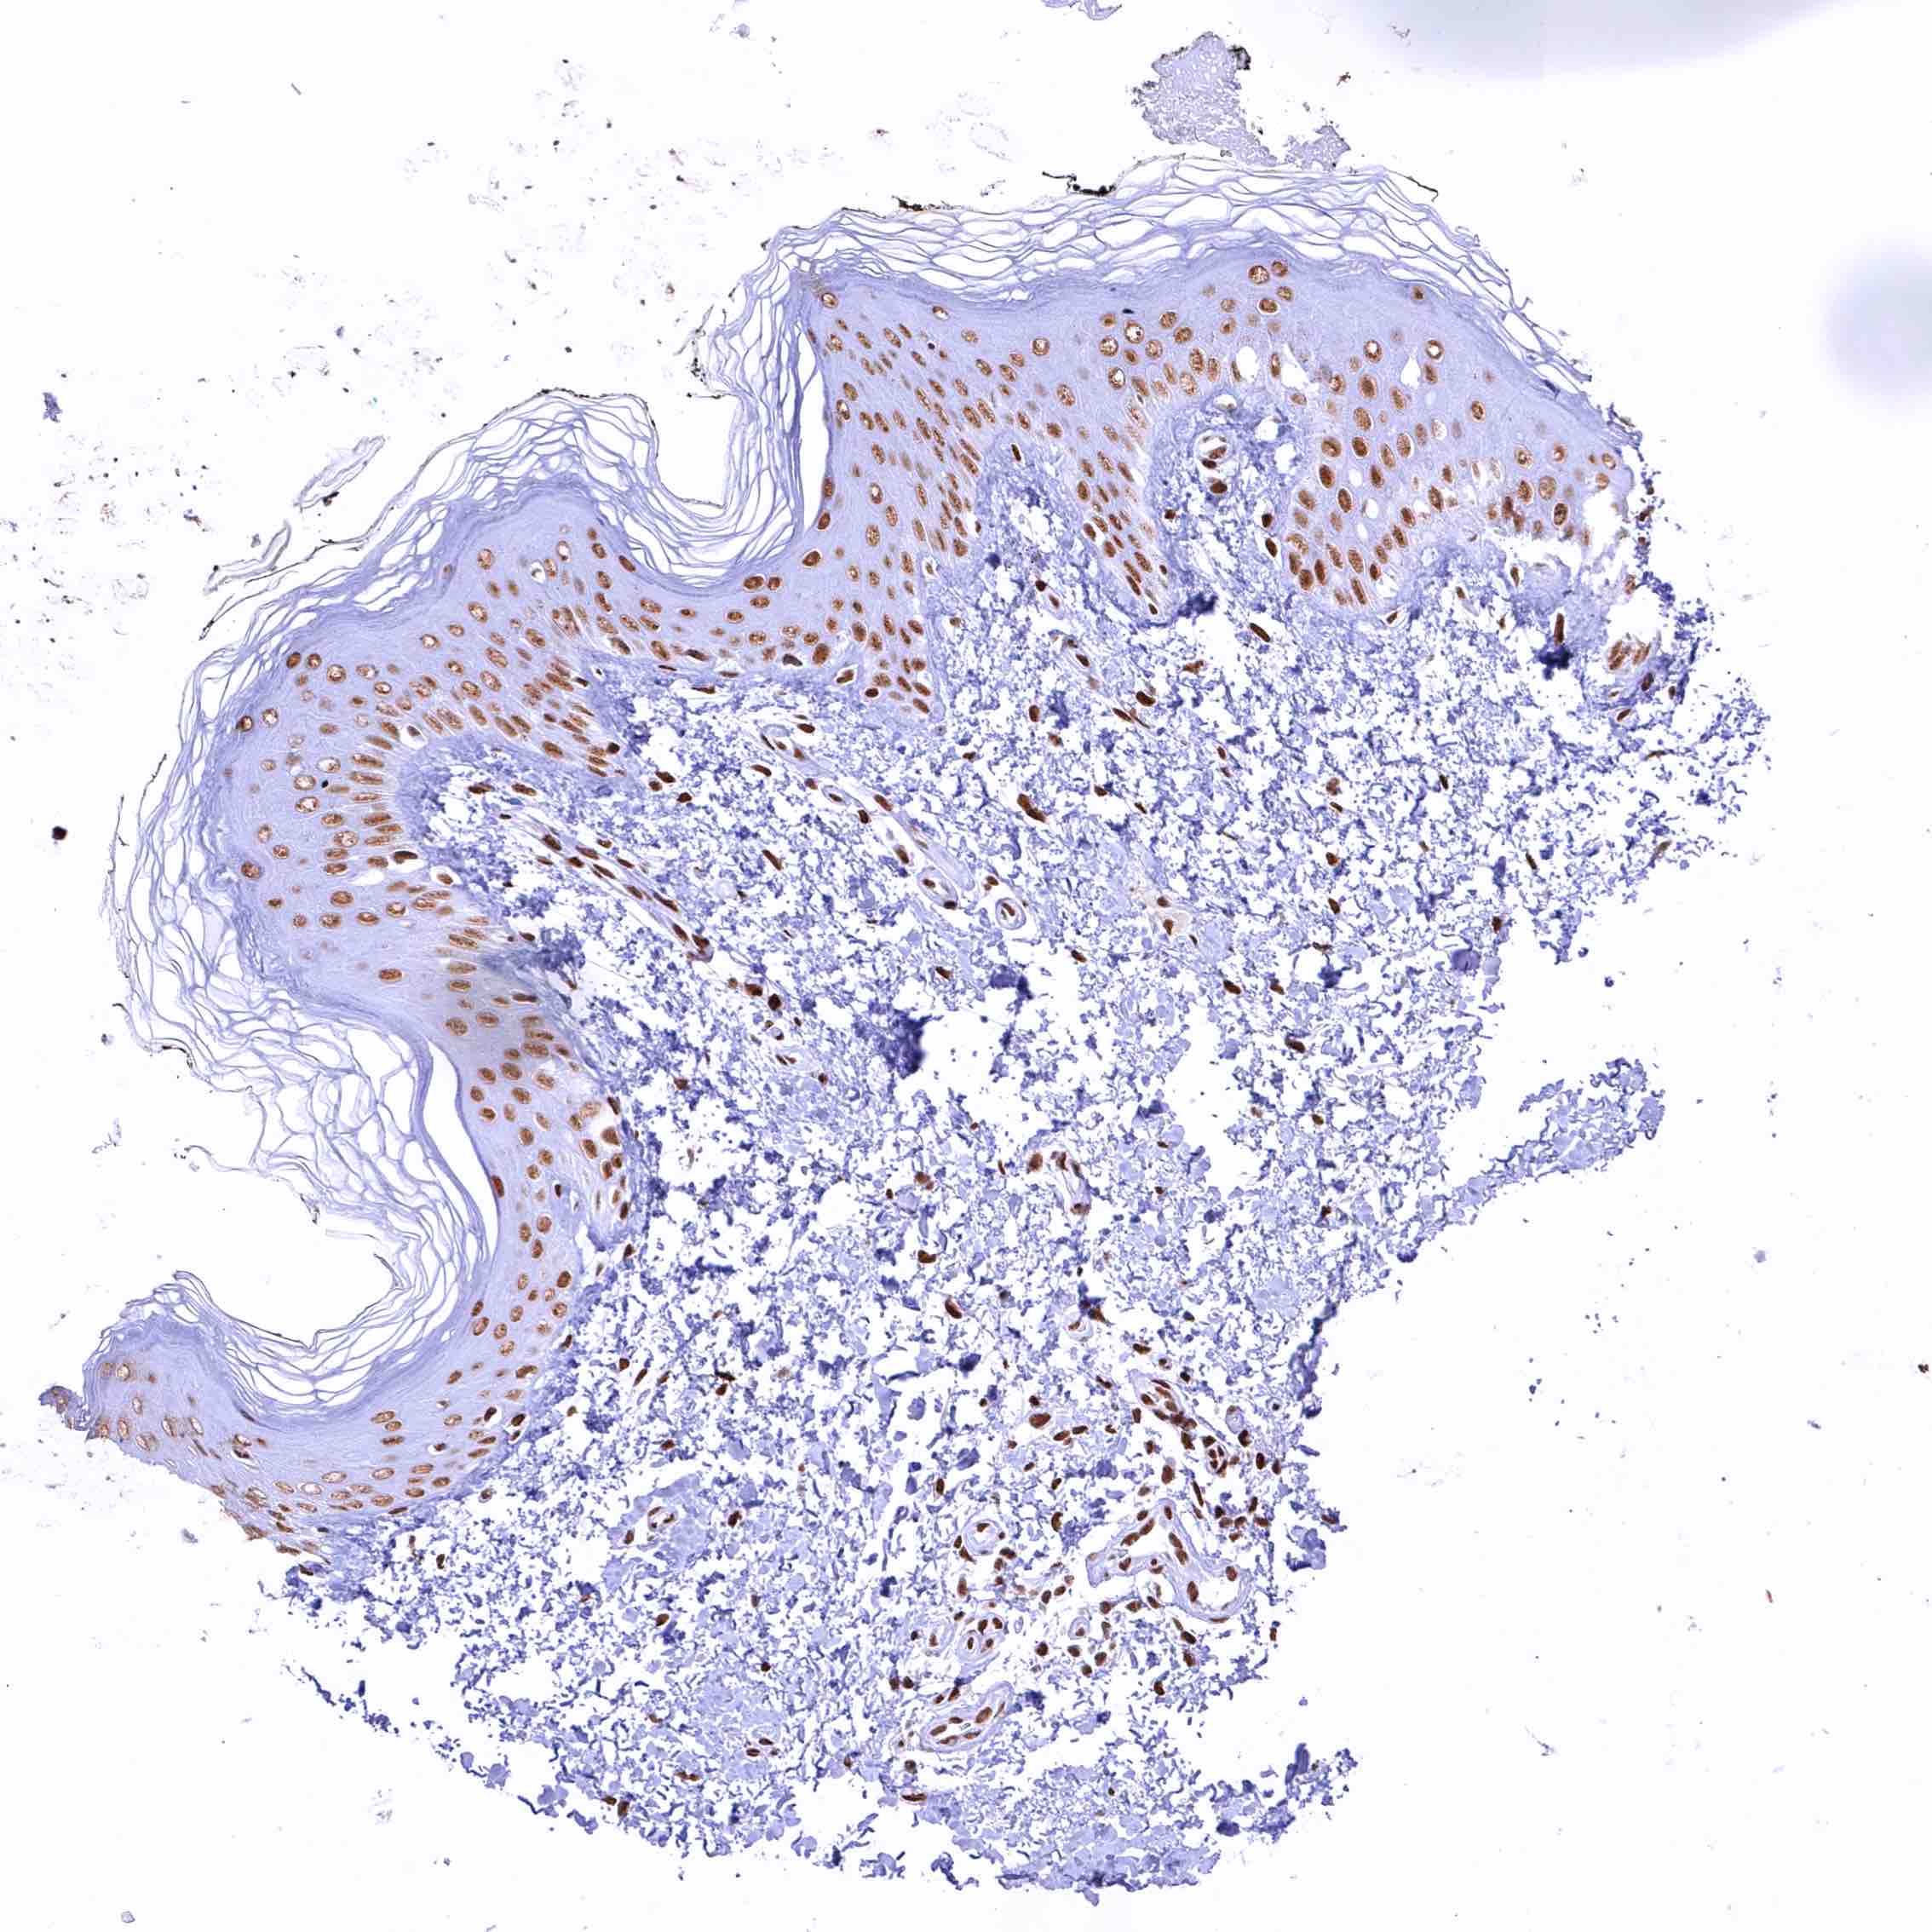

Skin – In squamous epithelium, the CBP staining intensity decreases slightly from the basal to the superficial cell layers

Skin, hairfollicel and sebaceous glands